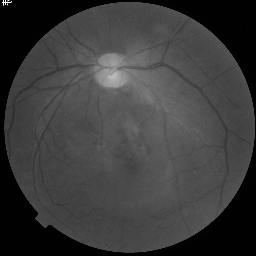

FIVES dataset [14] consists of 800 high-quality multi-disease fundus images and annotated segmentation masks. We partition this dataset into 70% for training (560 images), 10% for validation, and 20% for testing. Similar to ACDC, we use 5% (28 images) and 10% (56 images) of the 560 training images as labeled data to simulate low-data availability, treating the remaining data as unlabeled.

Synthetic Data: For our experiments, high-fidelity synthetic images are generated using StyleGAN2-ADA [16] as described in Section 3.1.2. The model is trained exclusively on the limited percentage of real labeled data available for each dataset (e.g., 5% or 10%). For instance, when using 10% labeled data (136 images for ACDC or 56 for FIVES), StyleGAN2-ADA is trained solely on these specific images. Figure 3 shows random synthetic samples generated for both ACDC and FIVES datasets at 5% and 10% labeled data splits.

To augment the limited real labeled data, high-fidelity synthetic images are generated using StyleGAN2-ADA [16]. The model’s Adaptive Discriminator Augmentation (ADA) mechanism dynamically adjusts augmentation probability to prevent discriminator overfitting on limited training samples, enabling realistic and diverse image generation even from minimal input. Figure 3 presents random selected synthetic images for the ACDC and FIVES datasets at the 5% and 10% labeled data splits.

We train StyleGAN2-ADA on the aforementioned 5% or 10% real labeled data. The quantity of generated synthetic images matches the remaining proportion of the full dataset (e.g., 90% or 95%), effectively serving as the unlabeled data input for the SRA-Seg framework.